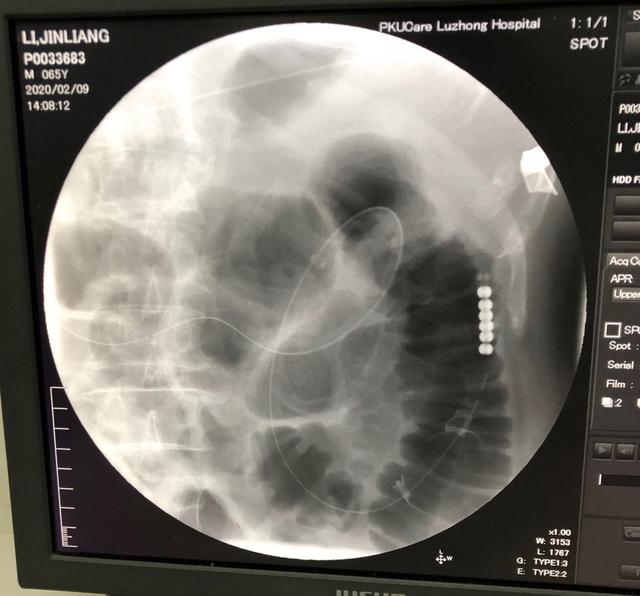

入院时,李大爷已有明显的腹痛、腹胀,伴有胸闷、心悸,恶心、呕吐等症状。胸腹部 CT 检查诊断局限性肺不张、感染及胸腔积液。小肠明显扩张并见数个气液平面,伴有腹腔积液。

孙士东主任医师带领消化科团队经过仔细的病情分析和充分的风险评估,决定对其实施「胃镜下经鼻肠梗阻导管置入术」。手术过程顺利,无任何不良反应。术后予以加强营养支持、促动力药、低频脉冲治疗,24 小时导管下行约 170 cm,引流肠内容物约 2000 ml。